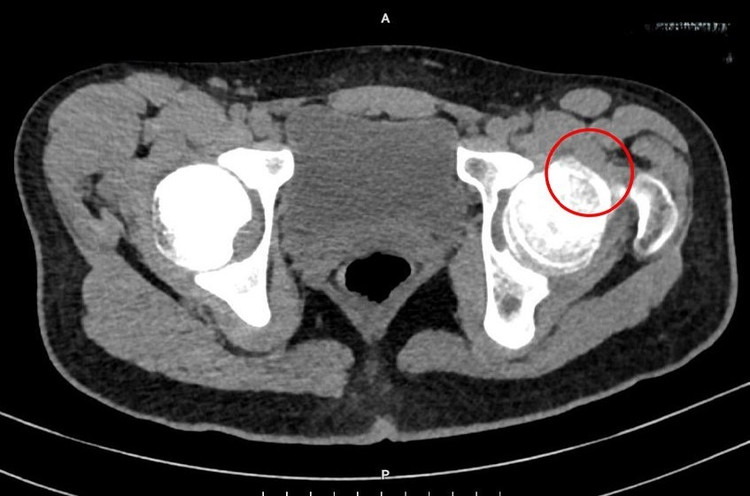

ThS.BS.CKI Nguyễn Xuân Trường, Trung tâm Chấn thương Chỉnh hình, Bệnh viện Đa khoa Tâm Anh TP HCM, cho biết kết quả siêu âm và chụp CT ghi nhận khớp háng bệnh nhi xuất hiện một mô xương bất thường, nhô cao, kích thước khoảng 5 x 10 mm, chiếm gần hết diện tích phía trước của chỏm xương đùi.

Hình chụp CT khớp háng bên trái, trên chỏm xương đùi có mô xương (khoanh tròn) nhô cao lên rõ rệt - Ảnh BVCC

Bác sĩ chẩn đoán P. mắc hội chứng cấn khớp háng. “Đây là một bệnh lý ít gặp, xảy ra khi xương hông phát triển bất thường không rõ nguyên do, làm xuất hiện một mảng xương nhô cao hơn ở chỏm xương đùi”, bác sĩ Trường nói thêm.